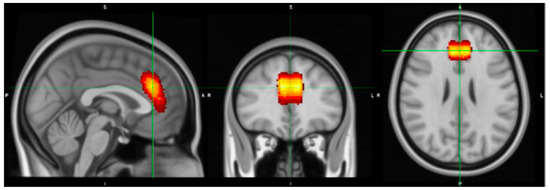

- Rorden, C.; Brett, M. Stereotaxic display of brain lesions. Behav. Neurol. 2000, 12, 191–200. [Google Scholar] [CrossRef] [PubMed]